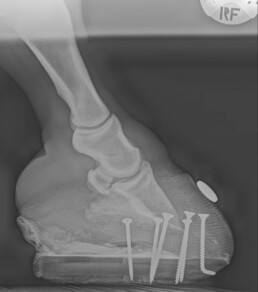

• Röntgenaufnahmen zur Beurteilung der Hufbeinlage

Bei Peter ergab das Röntgenbild eine Rotation der Hufbeine an beiden Vorderhufen, während die Hinterhufe unauffällig waren.